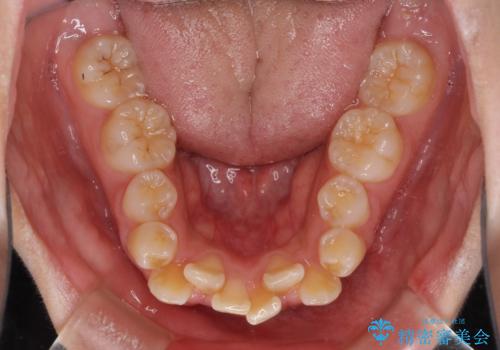

- 上下前歯の叢生と八重歯を気にして来院された患者様です。

前歯部叢生のスペースを獲得するため、上下顎左右小臼歯各1歯を抜歯することとしました。